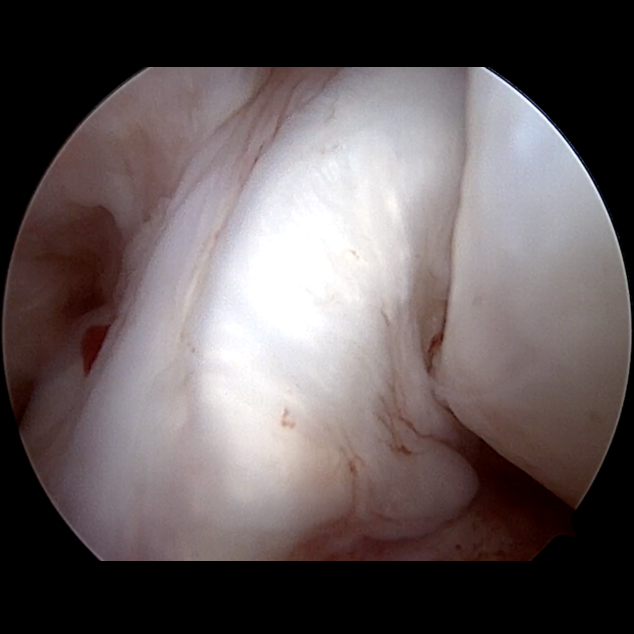

Die anatomische Bohrkanalpositionierung mit adäquatem Graftdurchmesser Durchmesser (in Abhängigkeit von der Notchgröße: ♀> 8 mm; ♂︎ > 8,5 mm) und die Adressierung der peripheren Stabilität sind die „Must Haves“ der modernen Kreuzbandchirurgie [18]. Unter Belassen der originären Kreuzbandfasern ermöglicht der ACL „remnant“-preserving Technique die Implantation des Grafts in die alten Fasern in der anatomischen Positionierung. Aktuelle Reviewanalysen zeigen hierüber die schnellere Einheilung des Grafts („Maturation“) und sekundär geringere Reinstabilitätsraten bei vergleichbarer Komplikationsrate gegenüber der Standard-Kreuzbandoperation [13, 18 – 22].